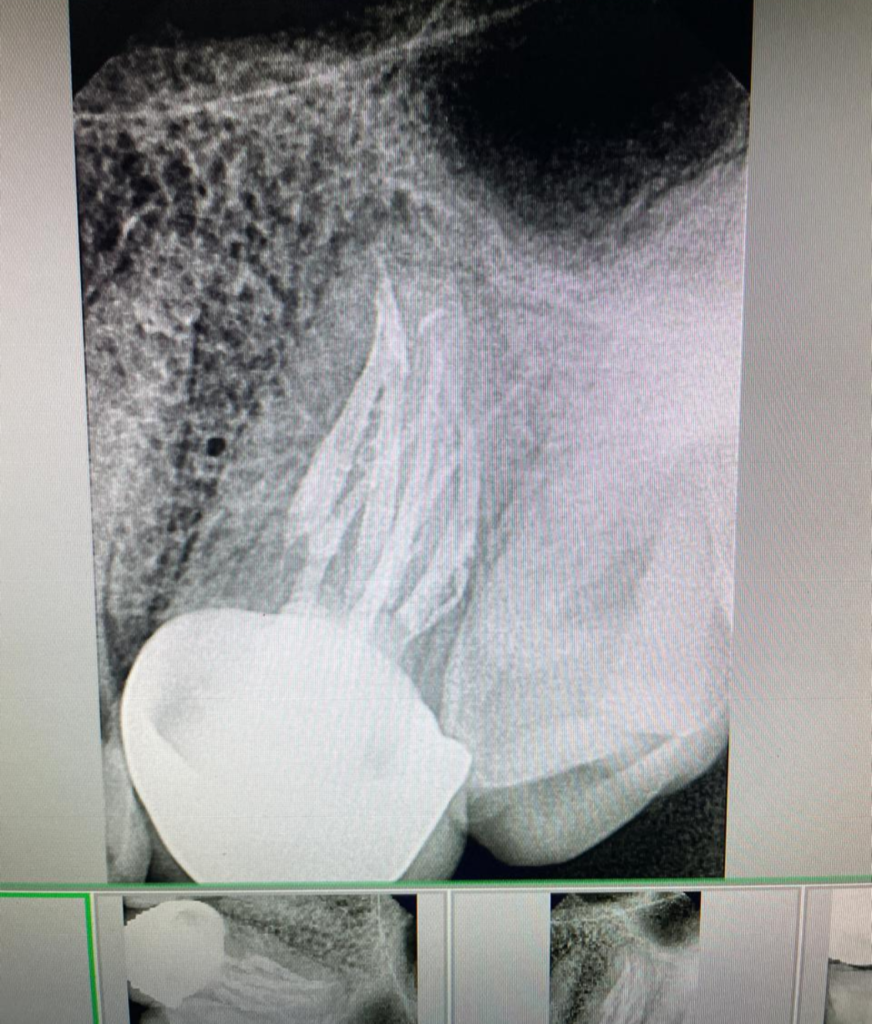

DOCTOR IN ACTION

Bilateral 6 canals in maxillary molars